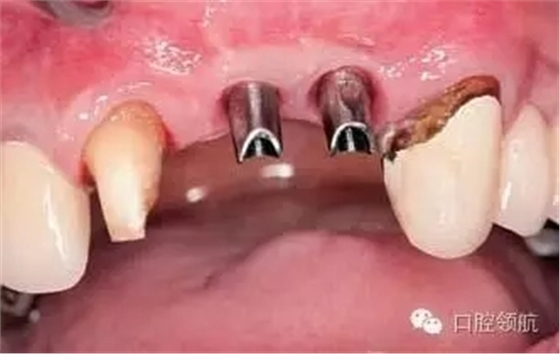

患者,53歲,男性,(右上第1、2顆牙) 缺失病例,由于牙槽骨高度不足,在行髂骨移植后進行了種植手術,但由于移植骨的吸收,種植體周圍的牙槽骨形態(tài)發(fā)生了變化引起了與對側同名牙的齦曲線明顯不對稱(圖1)。

圖1 去除愈合基臺后,由于移植骨的吸收,種植體周圍骨組織形態(tài)產生變化,引起與對側同名牙齦曲線明顯不對稱,作為解決的方案,提出通過外科手術再植骨和軟組織移植的方法以改善嵴頂?shù)拿缹W形態(tài)或使用修復方法來改善軟組織的美學效果。以上兩種方法供患者參考,最后患者選擇了修復的方法。